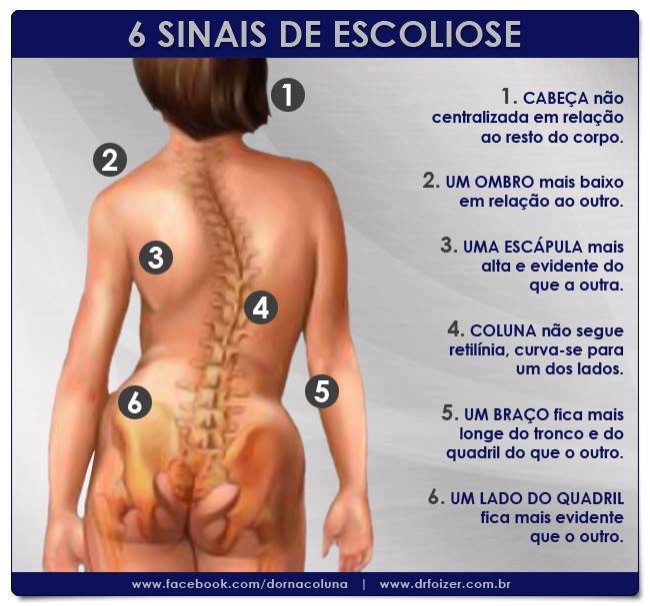

A deformidade causada pela inclinação e rotação das vértebras pode tornar-se perceptível ao observar a pessoa, principalmente pelas costas. Este é o principal sinal da escoliose e sua intensidade varia conforme:

- o tamanho da curva (ângulo de Cobb),

- o número de vértebras acometidas,

- e o grau de rotação vertebral.

Quanto maior a magnitude da curva, maior tende a ser a percepção da deformidade.

A escoliose pode ser inicialmente percebida pela observação do tronco. Muitas vezes, a mãe, o pai ou outro familiar nota uma assimetria, como diferença entre os lados do corpo em relação aos braços, à cintura ou aos ombros. Em alguns casos, observa-se também uma proeminência das costelas, próxima a um osso chamado escápula.

Desse modo, durante a avaliação médica, o ortopedista observa esses sinais e realiza um exame físico específico chamado Teste de Adams. Nesse teste, o paciente inclina o tronco para frente, flexionando a coluna torácica e lombar, sem dobrar os joelhos. Nos casos em que existe escoliose estrutural, torna-se visível uma elevação assimétrica das costelas, conhecida como giba costal.